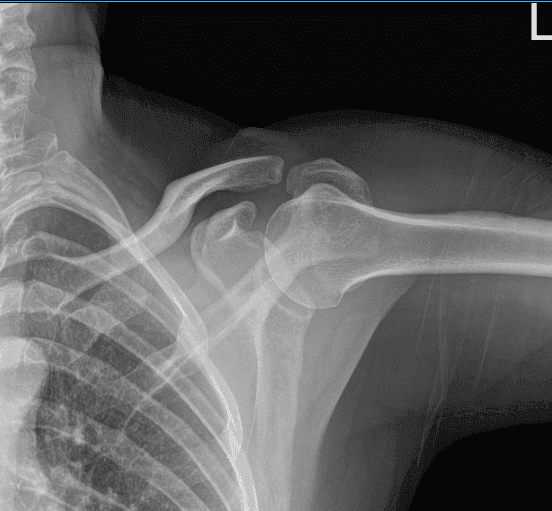

Hoy el paciente está aquí con quejas de dolor en el hombro izquierdo. No está seguro de cómo se hizo la lesión. El paciente trabaja a tiempo completo como capataz y ayuda a su compañero a levantar materiales pesados la mayor parte del tiempo.

Está aquí con una radiografía del hombro izquierdo. Es dominante en la mano izquierda. No puede trabajar debido al dolor. Ha probado a estirarse en casa y a tomar paracetamol, sin ningún beneficio.

Su radiografía mostró radiografías normales del hombro izquierdo, así que decidimos hacernos una resonancia magnética para ver la causa del dolor.